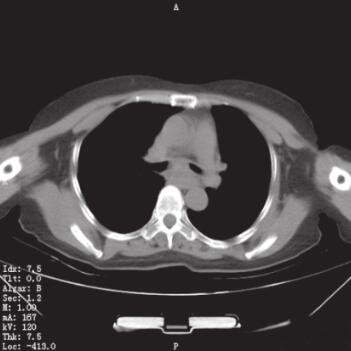

入院后检查:生命体征平稳,慢性病容,呼吸急促,口唇及甲床不发绀。上肺部可闻及双相哮鸣音,以吸气相为主,心率90次/分,律齐,各瓣膜听诊区未闻及杂音,肝脏、脾脏在肋缘下未能触及,剑突下无压痛,双下肢不水肿。血常规:WBC 7.66×109/L,N% 75.0%,HGB 135g/L,PLT 290×109/L。红细胞沉降率23mm/h。肝肾功能、生化未见异常。血气分析提示:pH 7.42,PaO2 80mmHg(1mmHg=0.133kPa),PaCO2 38mmHg。凝血指标及D-Dimer定量检测均在正常范围。入院后复查肺部CT(图1)。

图1 入院后肺部CT表现

A.隆突下肺窗显示隆突稍增宽;B.肺窗显示左肺舌叶炎性改变;C.隆突下纵隔窗显示隆突稍增宽

CT报告为左肺舌叶炎性改变,未见明确的占位性病变,考虑患者无咳痰,体温正常,血常规正常,无临床感染依据,未给予抗感染治疗,与家属进行沟通后决定完善电子支气管镜检查并在左主支气管新生物处取得病理组织。

5. 气管镜检查确诊后再次复习肺部CT表现,发现隆突较正常水平稍有增宽。本患者经过气管镜检查最终得到了确诊,但是家属拒绝进一步诊治使我们感到遗憾。